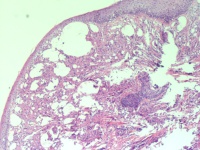

左侧眼睑肿物

性别

男

年龄

57岁

发现左侧眼睑肿物1月余

左眼睑肿物

0.3*0.2*0.2cm灰红肿物一枚

考虑:属于散粒肿的范畴